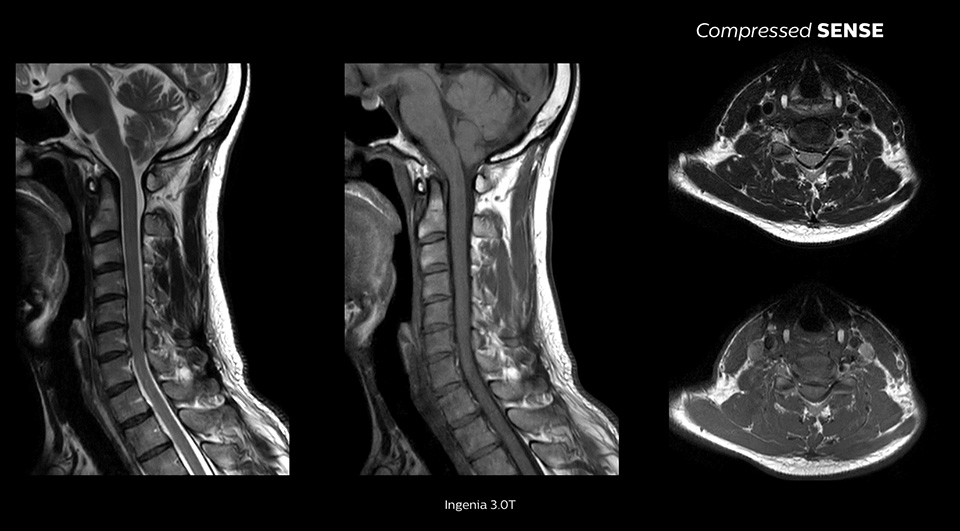

Estamos basicamente a executar os nossos protocolos padrão e apenas a ativar o Compressed SENSE e a ver uma redução de 20% no tempo de exame. Nenhum dos médicos sabe se é um exame Compressed SENSE versus um exame não Compressed SENSE quando estão a ler."

John P. Karis, M.D., Diretor de RM e imagiologia cerebral, Departamento de Neurorradiologia do Barrow Neurological Institute, EUA

Permite uma melhoria de até 64% na resolução espacial1